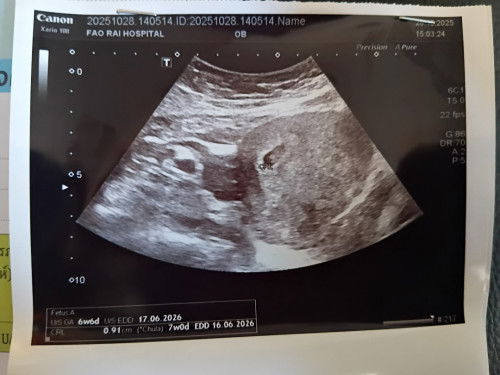

บ้านซาวตอน6วีคเจอแต่ถุงครรภ์.เมื่อวานครบ7วีคหมอนัดซาวอีกรอบเจอน้องแล้วค่ะแต่ตัวจิ๋วมาก😊😊

ฝากท้องครั้งแรก+ซาวด์ตอน7+2 wค่ะ เจอน้อง ถุงไข่แดงและใจเต้นแล้วค่ะ